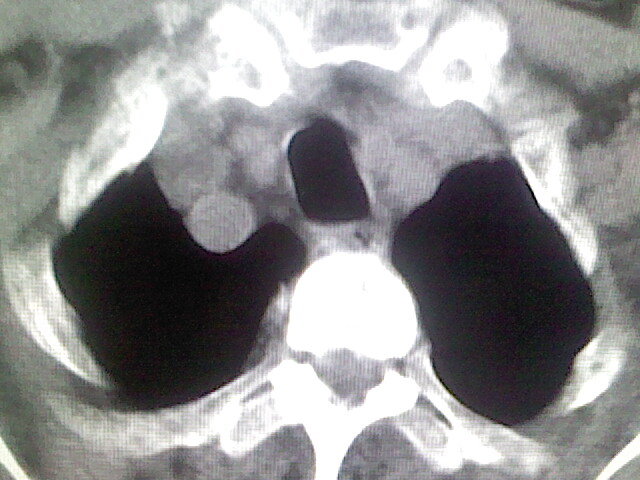

以下是引用zsl6918在2008-8-28 16:49:00的发言:[br]双肺炎性病灶,食管狭窄估计与心房增大压迫所致。

以下是引用xulianj在2008-8-28 20:36:00的发言:[br]慢支肺气肿伴感染,右上肺陈旧性结核;食道建议胃镜检查。

以下是引用wqs571018在2008-8-28 21:18:00的发言:[br]慢支继发感染,右上肺陈旧性结核;食道建议胃镜检查。